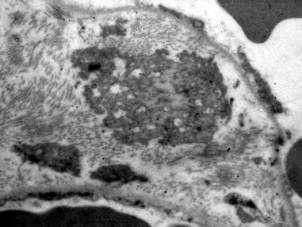

Патоморфологические изменения при гриппе и сепсисе в первые пять суток развития СОЛП характеризуются диффузным альвеолярным повреждением с усилением микропиноцитозного транспорта эндотелия, отеком интерстиция и резким субэпителиальным отеком. При сепсисе помимо указанных проявлений наблюдаются начальные явления фиброза аэрогематического барьера, что объясняется предшествующей, достаточно длительной для создания условий синтеза протеинов внеклеточного матрикса, системной воспалительной реакцией. Пролиферация и гиперплазия клеток альвеолярного эпителия гораздо раньше, чаще и с большей интенсивностью выявляется в случаях вирус-индуцированного заболевания. Этот факт объясняется тем, что при сепсисе, в отличие от вирусного, повреждение альвеолярного эпителия возникает вторично как следствие изменений интерстиция и базальной мембраны, а поэтому проявляется позже от начала регистрации клинических критериев СОЛП. Интерстициальный отек, и последующий интерстициальный фиброз по данным электронной микроскопии, более выражены при сепсисе, чем при гриппе, а признаки начинающейся карнификации имеют обратную взаимозависимость (Рис. 1, 2, 3, 4.).

Рис. 4. Электронная микро­фотография. Сепсис 14 суток. Зрелый фибробласт с морфологическими признаками деструкции находится в расширенном за счет отека и коллагенизации интерстициальном пространстве (стрелка). Ув. 6000.